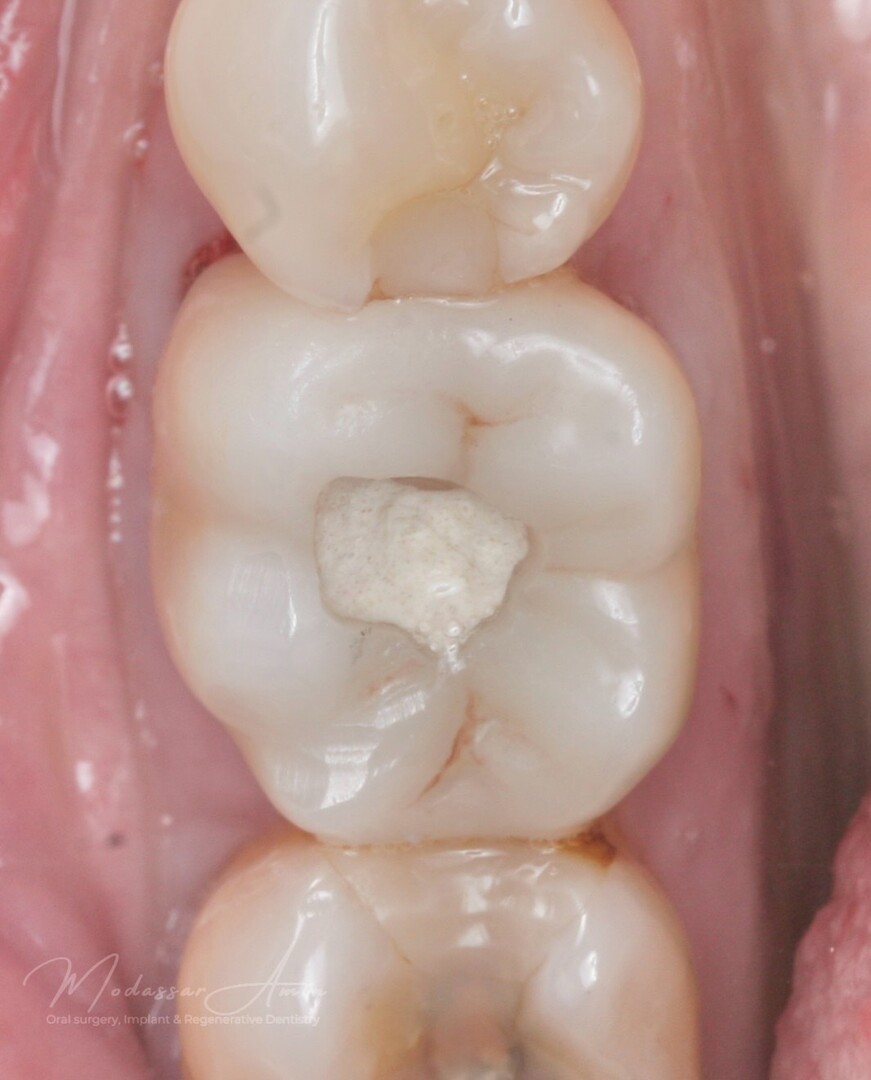

"Pasienten presenterte med tann 46 som ikke kunne bevares grunnet en dyptgående infraksjon inn i furkasjonen. Forholdene lå til rette for en immediate implantatbehandling. Ved hjelp av Versah osseodensifikasjonsbor ble det interradikulære beinet ekspandert på en skånsom og forutsigbar måte, noe som ga høy primærstabilitet (>40 Ncm) til tross for en lokal bendefekt apikalt mesialt etter kronisk apikal periodontitt. Den gode stabiliteten muliggjorde bruk av SSA (Sealing Socket Abutment) for forsegling. På grunn av tynn bløtvevsfenotype bukkalt ble behandlingen supplert med bindevevstransplantat (CTG)"

SSA (Sealing Socket Abutment) + CTG (bindvävstransplantat)